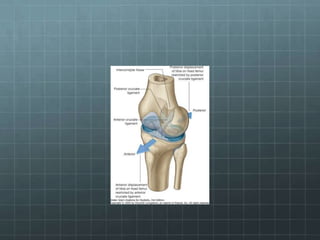

Ligamen pada sendi dapat dibagi dua yaitu

ligamen intracapsular dan extracapsular.

Ligamen intracapsular adalah ligamen yang

terdapat di dalam capsula articularis tapi tidak

di dalam cavum synovial (Ligamentum

Cruciatum Anterior dan Posterior).

Ligamen extracapsular adalah ligamen yang

terdapat di luar capsula articularis.

Anatomi

Genu

Meniskus

Lig. Cruciatum

Bursa

Ligament